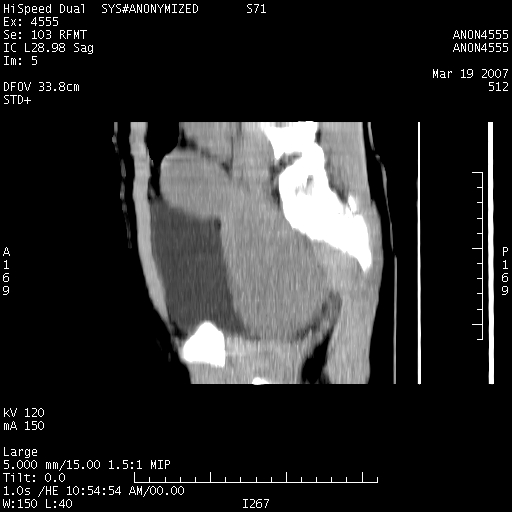

从矢状位上可见阴道部位明显增粗,内容密度较低,结合患者年龄和临床表现,首先考虑为先天性处女膜闭锁。

女,14岁,腹痛腹胀月余,患者发育正常,无月经史,检查发现下腹部肿块。患者碘过敏试验阳性。

考虑为先天性处女膜闭锁所致的阴道及子宫积血